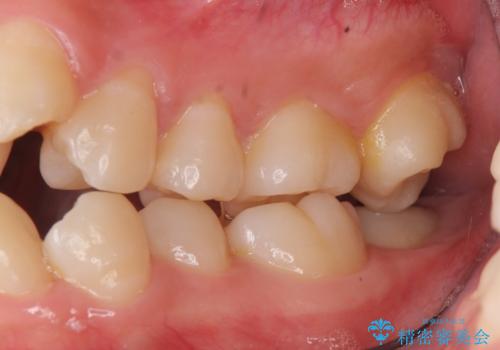

前歯は重度のがたつき、また奥歯はすれ違っていました。

治療は3年以上かかりそうと説明しましたが、2年台で終わらせることができました。

上下左右4本抜歯の可能性を説明していましたが、実際は上顎2本の小臼歯抜歯で済みました。

矯正用インプラントを使用して治療しています。